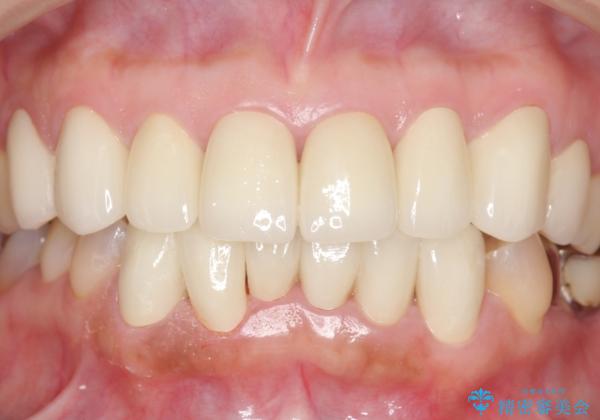

[ セラミック治療 ] 前歯の見た目を改善したい

- 前歯の色がばらばらで見た目が気になる、見た目の改善を希望され来院されました。

既に装着されていた金属を用いたセラミッククラウンの暗い色調とご自身の歯を白く、改善されたいと強く希望され

上下の前歯12本のセラミック治療を行なっていくこととなりました。

- 79.2万円(ジルコニアクラウン×6・仮歯×6)費用は治療当時の料金となります

セラミック治療を行うことで、若干の歯並びのがたつきも改善することができました。

![[ セラミック治療 ] 前歯の見た目を改善したいの治療後](https://seimitsushinbi.jp/wp/wp-content/uploads/2025/10/IMG_9934-500x350.jpg?v=1761816431)